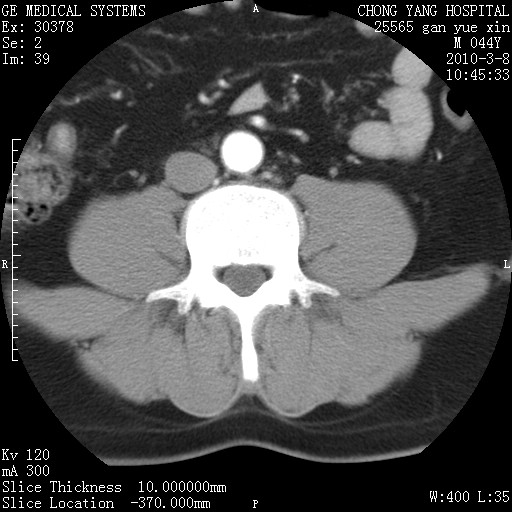

标题: CT24940:主动脉增强,典型病例。 [打印本页]

标题: CT24940:主动脉增强,典型病例。

夹层动脉瘤。

动脉夹层

夹层动脉瘤,典型

主动脉夹层。

动脉夹层的分型:

⒈debakey分型:根据主动脉夹层累及部位,分为三型:ⅰ型:原发破口位于升主动脉或主动脉弓部,夹层累及升主动脉、主动脉弓部、胸主动脉、腹主动脉大部或全部,少数可累及髂动脉。ⅱ型:原发破口位于升主动脉,夹层累及升主动脉,少数可累及部分主动脉弓。ⅲ型:原发破口位于左锁骨下动脉开口远端,根据夹层累及范围又分为ⅲa,ⅲb。ⅲa型:夹层累及胸主动脉。ⅲb型:夹层累及升主动脉、腹主动脉大部或全部。少数可累及髂动脉。

⒉stanford分型:a型:夹层累及升主动脉,无论远端范围如何。b型:夹层累及左锁骨下动脉开口以远的降主动脉。

夹层动脉瘤,少量胸水

夹层动脉瘤;左侧少量胸腔积液。

典型主动脉夹层。